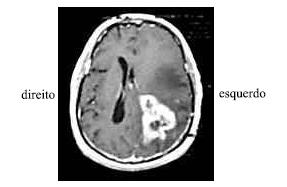

Uma senhora de 55 anos de idade, viúva, diabética e hipertensa, deu entrada no pronto-socorro após ter desmaiado em sua casa. O seu neto de 9 anos de idade informou que viu a avó cair da própria altura enquanto ela ia se contorcendo, tendo, depois, se debatido no chão e não acordado mais. Ao exame inicial, a paciente apresentava-se não-responsiva aos comandos verbais, movimentava os membros esquerdos, mas só retirava os membros direitos aos estímulos dolorosos (sem postura patológica). Foi verificada anisocoria sutil, com a pupila esquerda maior que a direita. A família referiu ao clínico geral que a paciente estava cada vez mais confusa nas últimas semanas, e atribuiu tal fato aos descuidos da paciente com o diabetes.

Considere que a paciente referida no texto, ao se encontrar estável, tenha sido submetida a uma ressonância nuclear magnética com contraste, cujo resultado é mostrado na figura acima. Diante do quadro clínico em tela, assinale a opção acerca da conduta mais adequada em relação a essa paciente.